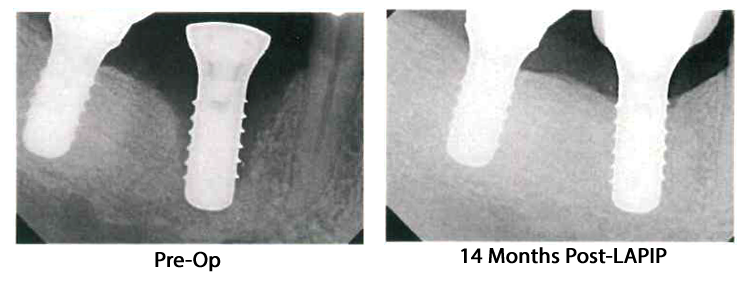

The only solution for a failing implant required surgery - until recently. LAPIP, which stands for Laser Assisted Peri-Implant Procedure is the only FDA approved and cleared procedure to treat ailing/failing implants.

Click here to see before and after photos of LAPIP Click here to read more about LAPIPAt our practice, we're dedicated to empowering patients with healthy smiles and the confidence that comes with them. We understand the trust you place in us, and we prioritize creating personalized treatment plans to achieve your oral health goals.